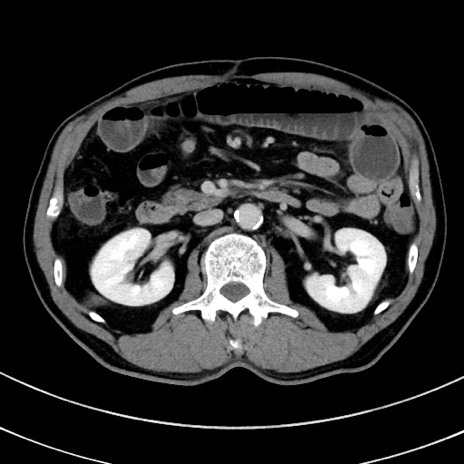

症例8(横断像)

【症例】 60歳代男性

【主訴】 黒色吐物

【現病歴】 4日前から嘔気自覚、2日前の朝食後にも嘔気あり、自分で手で嘔吐反射起こし嘔吐したところ血が混ざっていたため受診。

【既往歴】 5年前汎発性腹膜炎を伴う急性虫垂炎で手術、高血圧、前立腺肥大症、高脂血症

【身体所見】 腹部正中に手術癩痕あり 腹部平坦・軟圧痛なし膨満感あり

【データ】WBC 8400、CRP 4.54